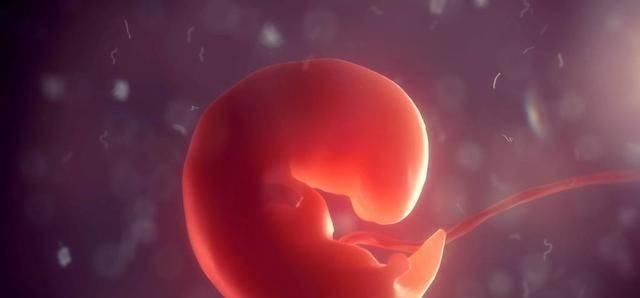

3、胎芽

很多朋友认为胎芽是胎儿身上的芽,其实不是,它指的是“胎儿本身”怀孕6周的时候,胚胎像松子仁难么大,但是原始器官、四肢雏形已经形成,医学上称它为“胎芽”。身体蜷缩成大“C”字,也很像一个芽。

B超可以测量胎芽的长度,这几周的标准如下: